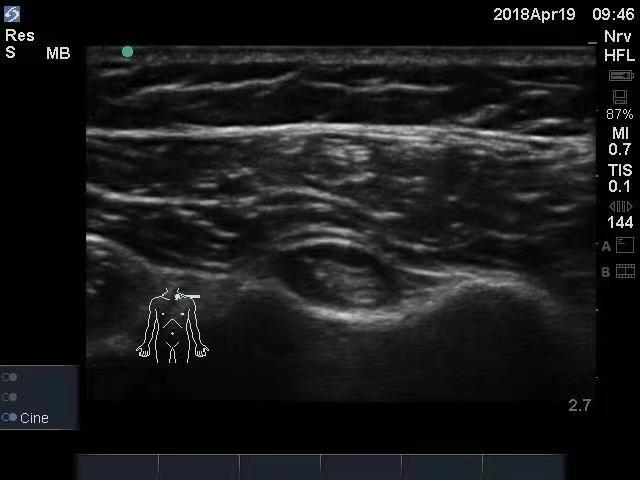

对该患者诊断明确后,我们对其采用基础用药方案:氟比洛芬凝胶贴膏加醋氯芬酸肠溶片进行抗炎止痛,并联合应用中枢性肌肉松弛药替扎尼定。 全身用药作用较慢,并不能够迅速消除该患者肩关节局部的炎症、水肿和疼痛,必须有一种方法能够直接作用于病变部位,快速改善症状,促进关节炎症的消除和肌腱损伤的修复。基于这些考虑,我们在超声引导下对患者进行肩关节注射治疗。 关于局部炎症损伤引起的疼痛,我们一般首选的局部注射药物是甾体类药物(曲安奈德、倍他米松或者地塞米松等)。 甾体类药物具有强大的抗炎作用,能够迅速消除炎症,改善水肿,减轻疼痛。但是,因为这个患者血糖控制不佳,可能针对其应慎用或者禁用甾体类药物。我们采用三氧治疗(又叫臭氧治疗)方法。三氧具有非常好的抗炎作用,它还能够氧化蛋白多糖,减轻滑膜水肿,并能够改善组织缺氧,直接止痛,是非常好的一个抗炎治疗方法。该患者进行三氧治疗后,炎症迅速消除,疼痛也明显缓解。 这个患者除了肩周炎,还有肩袖损伤,而肩袖损伤的修复相对困难。这些年来,在运动医学领域,PRP(富血小板血浆)注射治疗技术应用非常广泛,NBA(美国男子职业篮球联赛)湖人队球员霍华德就因为肩关节盂唇撕裂,接受了PRP注射治疗并取得了非常好的效果。PRP注射治疗是抽取患者自身血液,提取PRP,应用于患者自身,加速人体的自然愈合,促进骨和软组织再生。提取的这些PRP成分,不仅为组织修复提供了“浓缩的营养”,还为组织修复创造了更好的修复环境,能有效促进和加速组织修复。 我们借助疼痛科医生的“第三只眼睛”——超声,对该患者进行了三氧和PRP注射治疗。在超声下,可以非常清楚地看到病变部位,进行穿刺,能够准确地将穿刺针刺入相应的病变部位,达到靶点治疗的目的,并能够避免损伤血管神经等组织结构带来相应的不良反应。 这个患者最后的转归非常好,住院时进行了基础的药物治疗,在入院的第2天和第4天进行了肩关节三氧治疗后,疼痛评分迅速由中重度疼痛的6分降到了轻度疼痛的3分,然后在第6天和第13天分别进行了肩关节PRP注射治疗。出院时,患者的疼痛评分仅1分;一个月后随访,患者的疼痛基本消失。(作者供职于郑州大学第一附属医院)